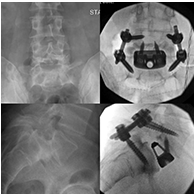

I had the privilege of operating on a 42-year-old gentleman with severe low back pain due to a high-grade spondylolisthesis at L5/S1. Read More